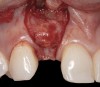

Fig 3. A patient presented with a high smile line and midfacial recession of the maxillary right lateral incisor as evidenced by the increased tooth length compared with the contralateral lateral incisor.

Figure 3

Fig 4. Intraoral view of tooth No. 7 with the gingival zenith more apical than the adjacent central incisor and canine tooth.

Figure 4

The following case report provides an example of this case scenario: A 28-year-old white female patient presented with her maxillary right lateral incisor significantly longer than the contralateral tooth following restoration of an existing crown that was 10 years old (Figure 3). The patient was dissatisfied with the esthetic appearance of the restoration due to the increased length, recession of the gingival tissues, and discoloration of the surrounding mucosa (Figure 4). Similar to case scenario No. 1, the first step in treatment was to decoronate the healthy implant by placing a flat surgical cover screw and employing a provisional resin-bonded-retained (RBR) prosthesis as a transitional fixed restoration (Figure 5 and Figure 6). The gingival augmentation in situ was allowed to take place for 2 to 3 weeks and was evaluated after that time (Figure 7).